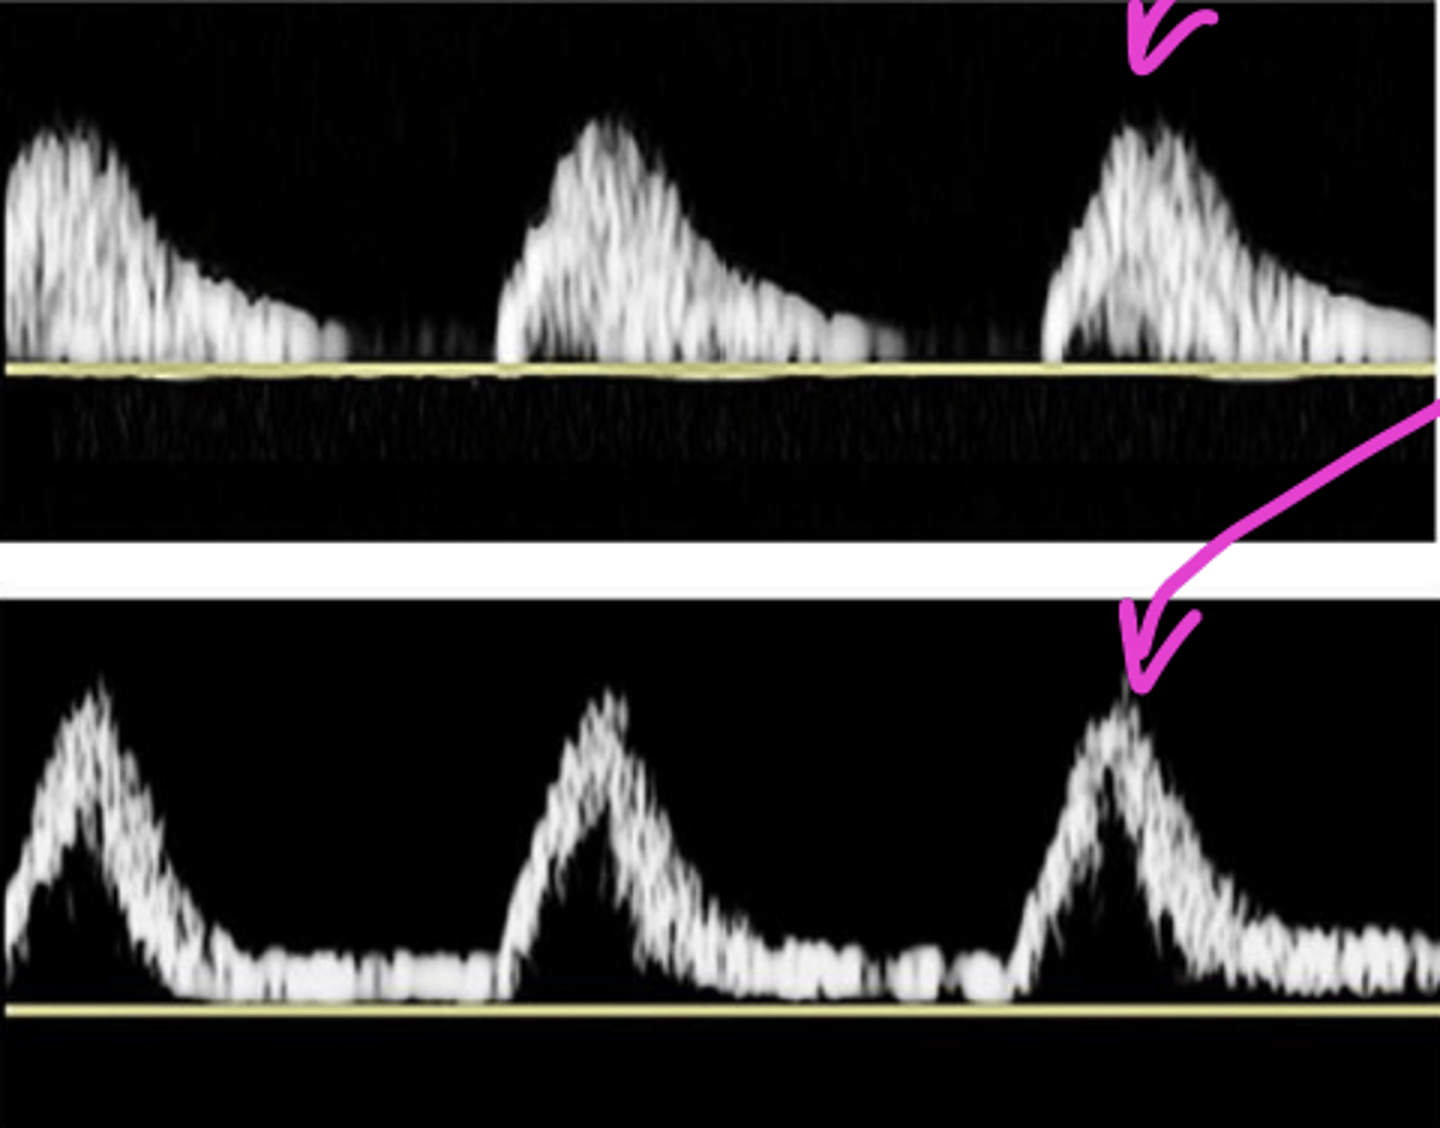

Resistance

High Resistance

sharp upstroke/brisk downstroke

Intermediate Resistance

-sharp upstoke/brisk downstroke

-forward flow throughout

-end systolic notch

Low Resistance

broad downstroke and continual flow through out diastole